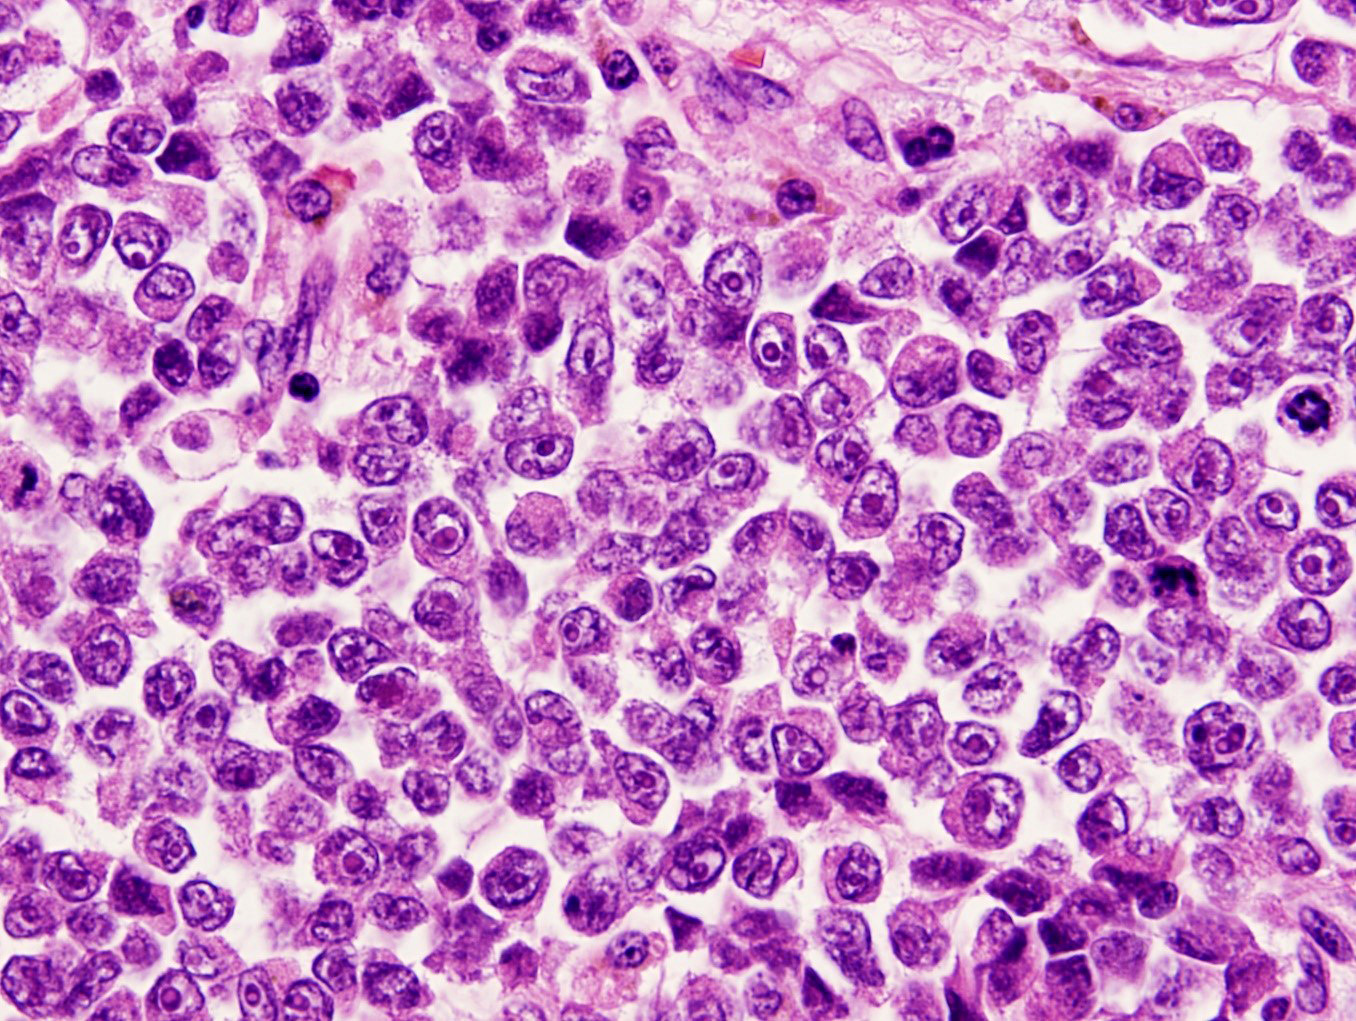

Microscopic (histologic) description

- Mostly epithelioid tumor cells with at least focal melanin pigment (Mod Pathol 2019;32:957)

- Associated melanoma in situ component (junctional melanocytic activity / junctional melanocytic component / tumor nests at the epithelium - lamina propria junction / horizontal tumor spread in the basal layer of the epithelium) and melanocytosis / melanosis (Mod Pathol 2019;32:957, Ann Thorac Surg 2013;96:1002)